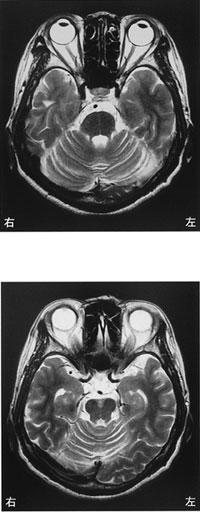

70歳の女性。ADLは一部介助でサークル型歩行器を用いて50 mの移動ができる。頭部MRIを示す。歩容としてみられるのはどれか。

1

はさみ足歩行

2

分回し歩行

3

中殿筋歩行

4

失調性歩行

5

鶏歩